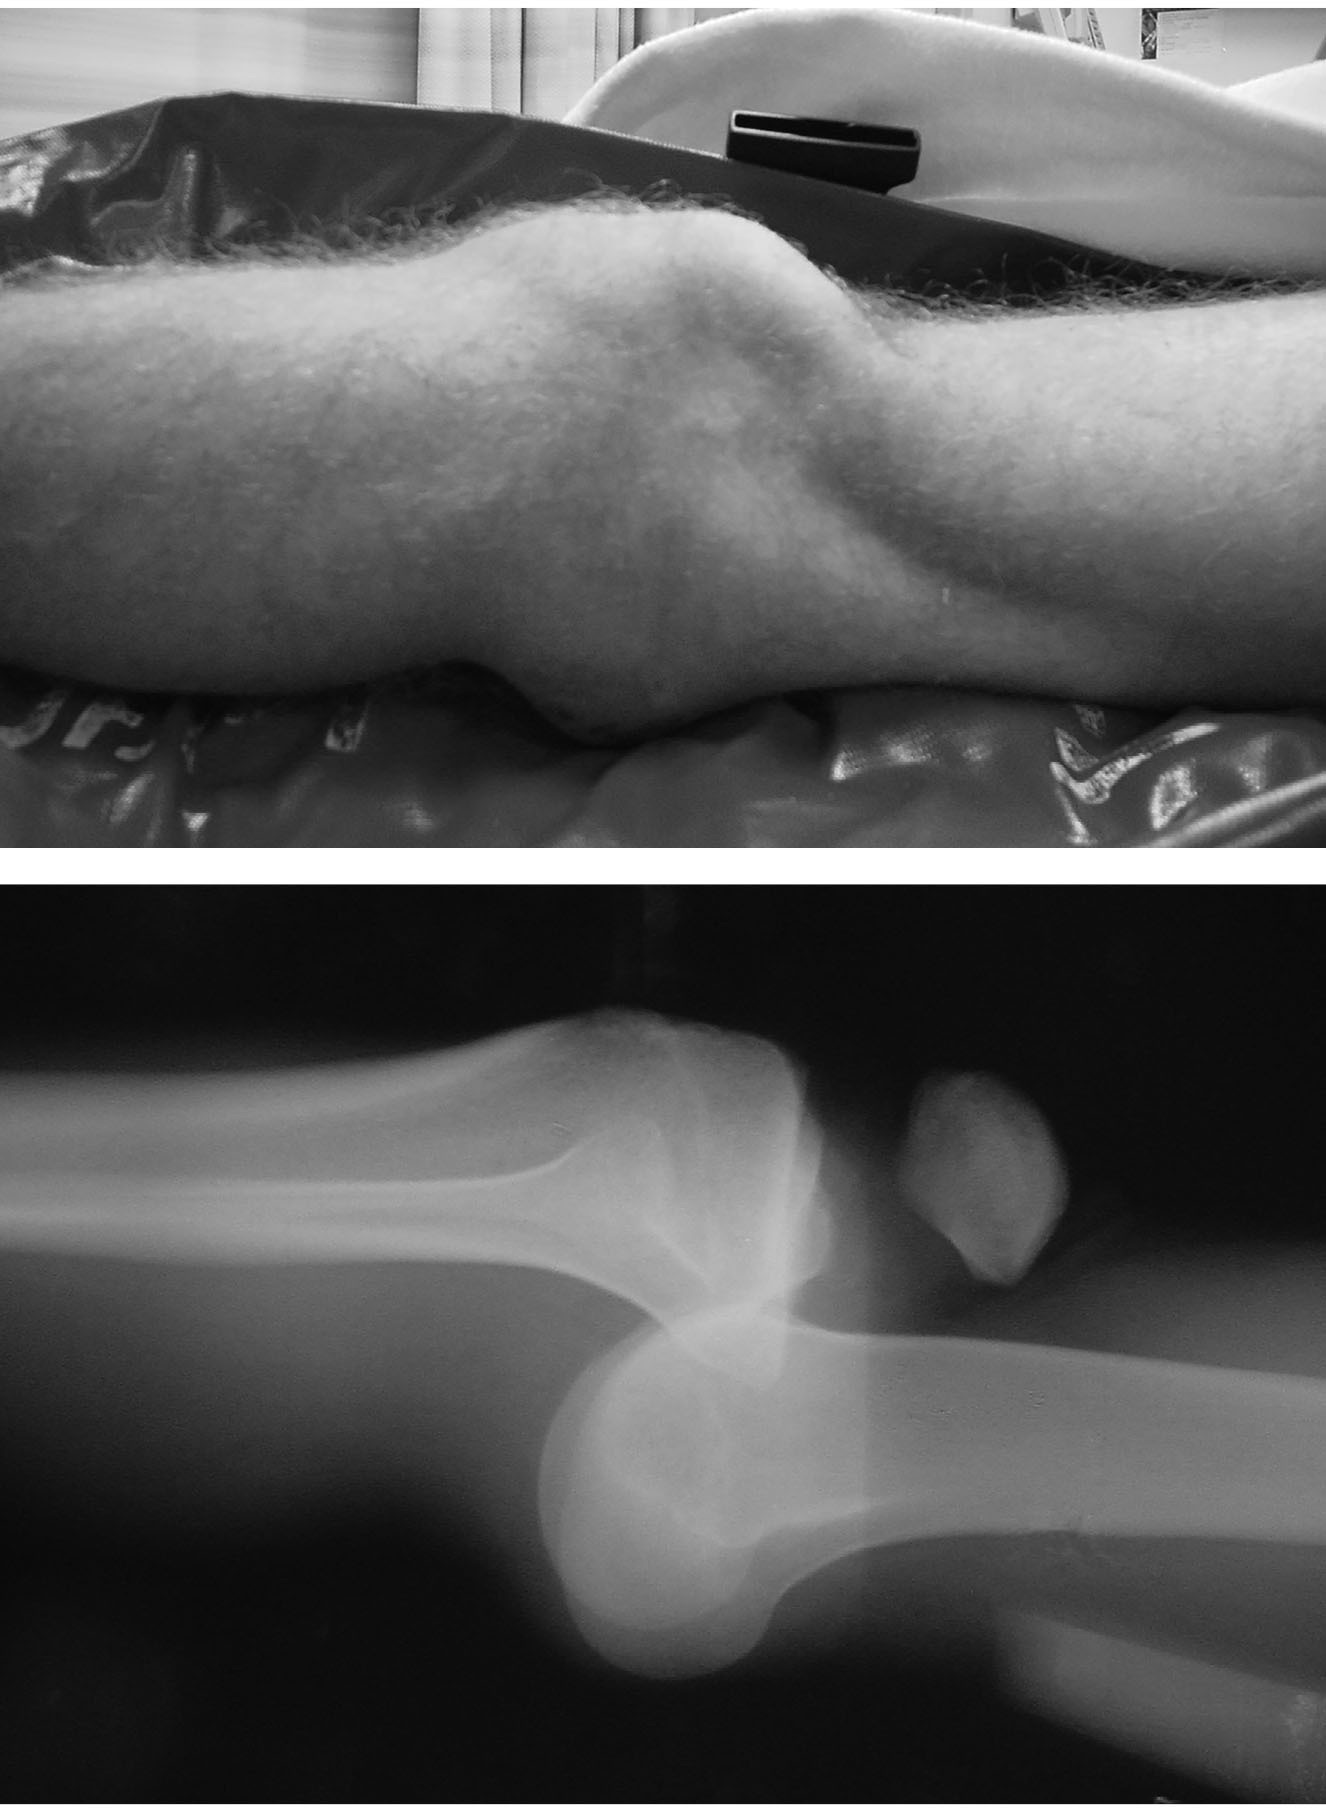

If the patient is neurovascularly intact, pre-reduction X-rays (anteroposterior [AP] and lateral views) should be obtained prior to reduction attempts.7 (See Figure 1.) Procedural sedation may not be required given the significant laxity associated with KDs. Once the knee has been reduced successfully, the patient should be placed in a long leg splint with the knee flexed 15-20 degrees, and post-reduction X-rays should be performed. Repeat neurovascular testing should be performed every two hours to ensure that delayed neurovascular injury does not develop.

Figure 1. Anterior Knee Dislocation Before Reduction |

![]() |

Images used with permission from Dr. J. Stephan Stapczynski. |